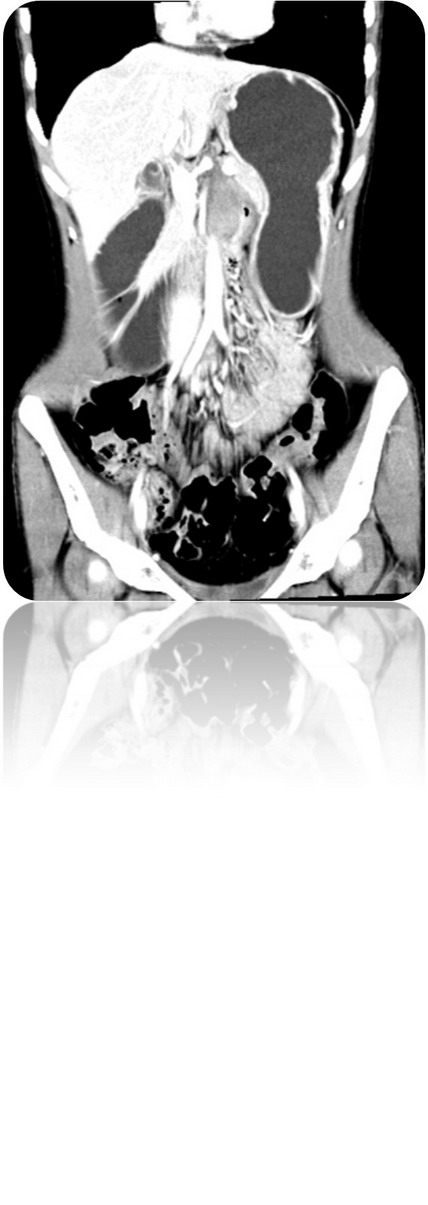

2009.6.23 腹部CT

腹膜后占位,性质待定,十二指肠局部穿透伴炎性包裹,十二指肠水平段梗阻,近端积液扩张,肝小囊肿(胰体后下方见不规则软组织密度影,大小约48mm*33mm,其内见气体密度影,增强扫描静脉期肿块明显不均匀强化,CT值约30HUPS 86HUCE,病变与十二指肠水平段、升段及胰腺分界不清,十二指肠水平段明显变窄,胃及近端十二指肠明显积液扩张。)